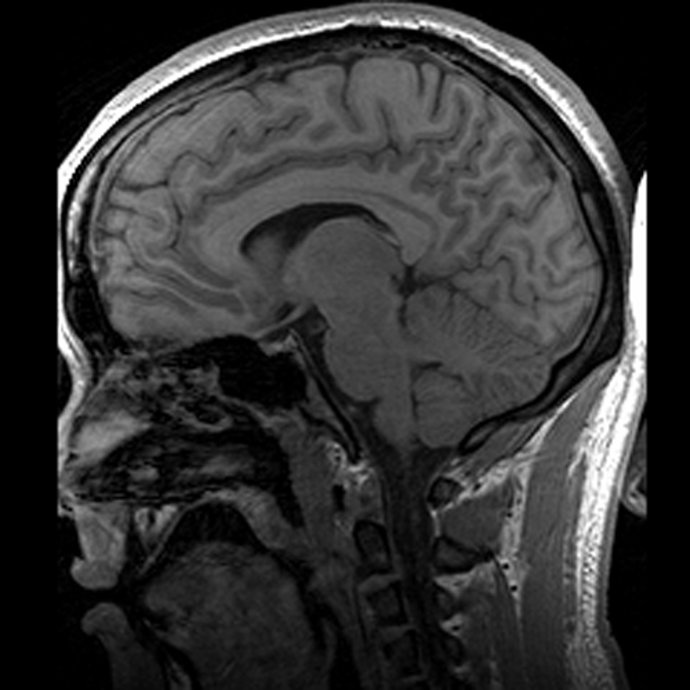

Un escáner cerebral para medir la capacidad de liderazgo

cerebro, escáner

Un equipo de neurocientíficos, psicólogos y expertos en Gestión de la Universidad de Reading, en Reino Unido, están colaborando en un estudio con el que pretenden averiguar si es posible detectar la capacidad de liderazgo de los ejecutivos mediante un escáner cerebral.

Para ello, una serie de directivos de empresas se han sometido a una resonancia magnética al tiempo que completan por ordenador una serie de ejercicios sobre decisiones financieras. "Lo que se les pide es que decidan si, en función de cierta información, es mejor tomar una decisión a corto o largo plazo", añade el profesor Douglas Saddy, que también colabora en el estudio.

De este modo, mientras el ejecutivo presiona el teclado se mide su actividad cerebral y, junto con el resultado de estas pruebas y otros escáneres, se intentarán extraer algunas conclusiones.